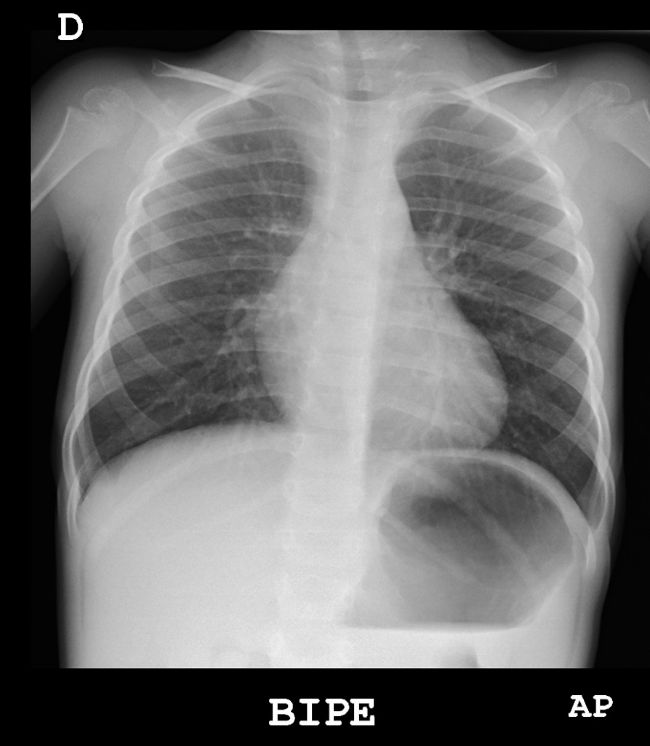

Radiografía AP de tórax normal en niño de tres años

En el estudio de la patología respiratoria en el niño, la radiografía (Rx) de tórax es la primera técnica de imagen a realizar. De forma rutinaria, en la edad pediátrica se realiza exclusivamente la radiografía anteroposterior (AP), o posteroanterior en los niños más mayores, reservando la proyección lateral para dudas razonables en la AP. Habitualmente, los estudios en niños colaboradores se realizan en bipedestación, mientras que en los más pequeños se realizan en decúbito supino1.

Debemos respetar el principio as low as reasonably achivable (ALARA), empleando la menor cantidad de radiación posible para un correcto diagnóstico. En Pediatría, habitualmente solo solicitaremos radiografías AP e intentaremos reducir el número de exploraciones necesarias.